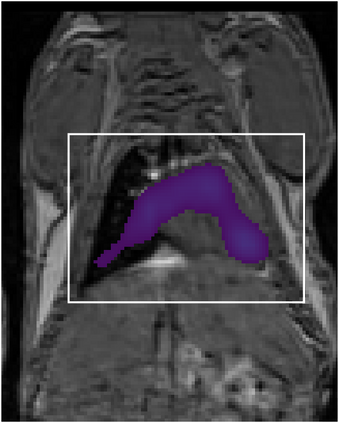

Various imaging modalities allow for time-dependent image reconstructions from measurements where its acquisition also has a time-dependent nature. Magnetic particle imaging (MPI) falls into this class of imaging modalities and it thus also provides a dynamic inverse problem. Without proper consideration of the dynamic behavior, motion artifacts in the reconstruction become an issue. More sophisticated methods need to be developed and applied to the reconstruction of the time-dependent sequences of images. In this context, we investigate the incorporation of motion priors in terms of certain flow-parameter-dependent PDEs in the reconstruction process of time-dependent 3D images in magnetic particle imaging. The present work comprises the method development for a general 3D+time setting for time-dependent linear forward operators, analytical investigation of necessary properties in the MPI forward operator, modeling aspects in dynamic MPI, and extensive numerical experiments on 3D+time imaging including simulated data as well as measurements from a rotation phantom and in-vivo data from a mouse.